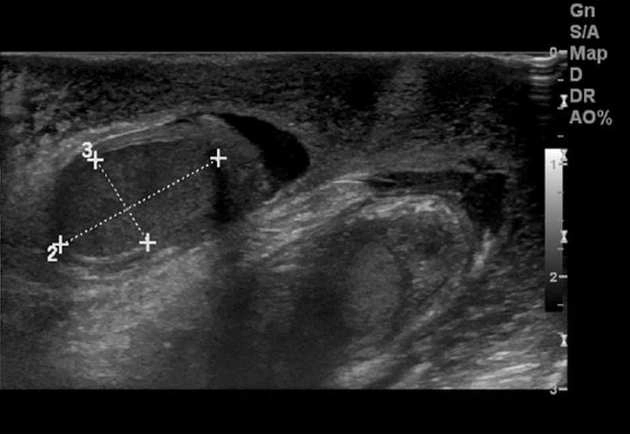

• Bìu và thừng tinh

• Bệnh lý viêm nhiễm

Tràn mủ tinh mạc (Scrotal pyocele)

16/03/2026